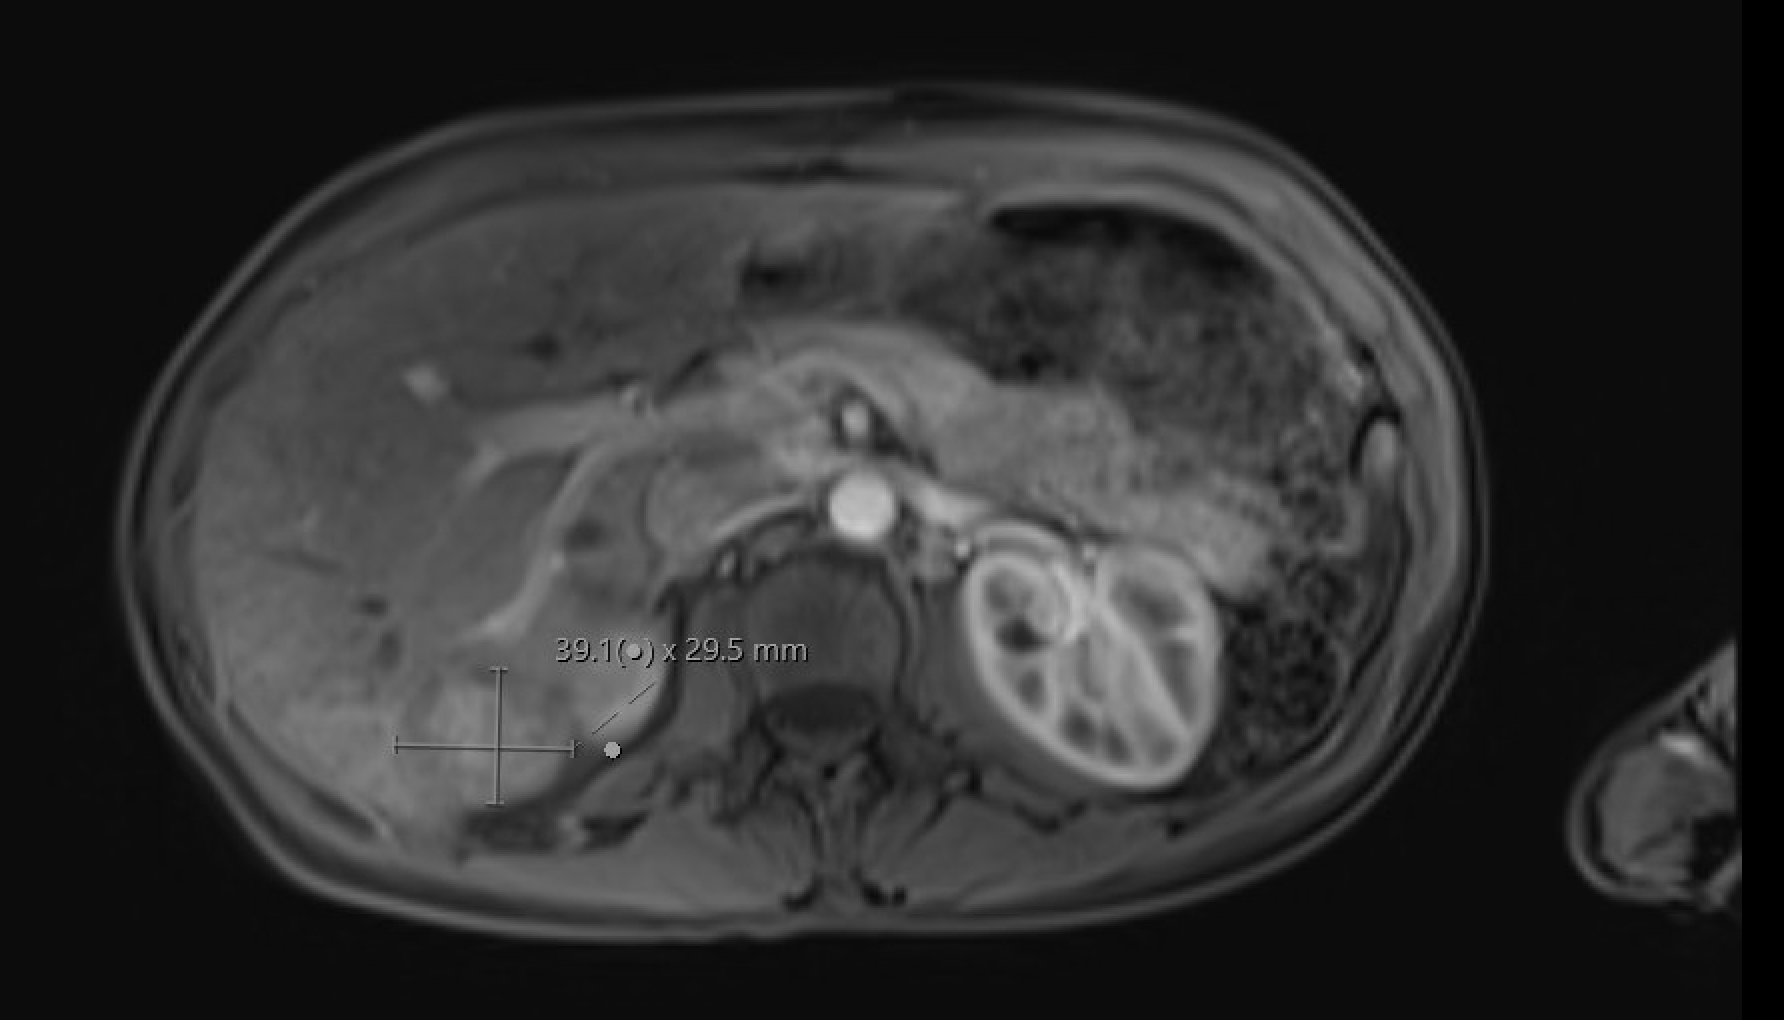

Spontaneous renal hemorrhage

(Wünderlich syndrome)

Subcapsular/perirenal T1-hyperintense collection with T2 signal heterogeneity. Subtraction images mandatory to exclude underlying enhancing neoplasm (AML, RCC most common causes)